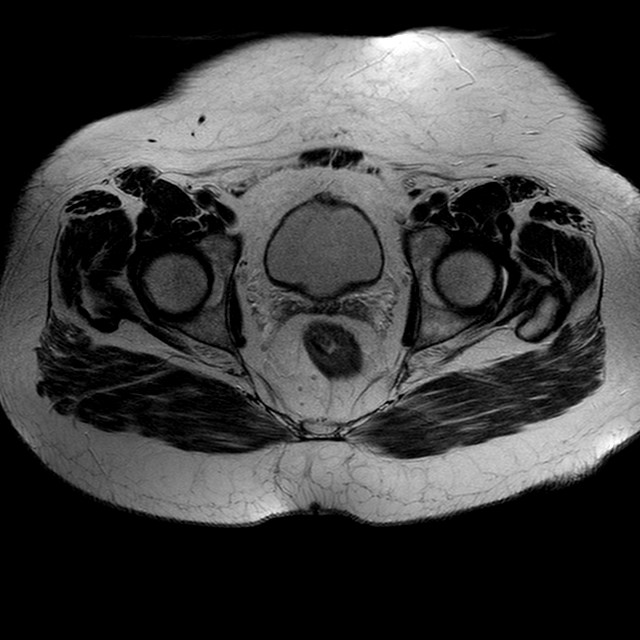

Esami: RMN BACINO

T2w TSE

Evidenti e simmetriche alterazioni osteofitosiche in regione coxo femorale con riduzione delle rime articolari. Degenerazione completa del cercine glenoideo. Non attuali segni di versamento articolare. Non segni di edema osseo che escludono attuale algodistrofia od osteonecrosi. Lieve e simmetrica riduzione del trofismo della muscolatura glutea.